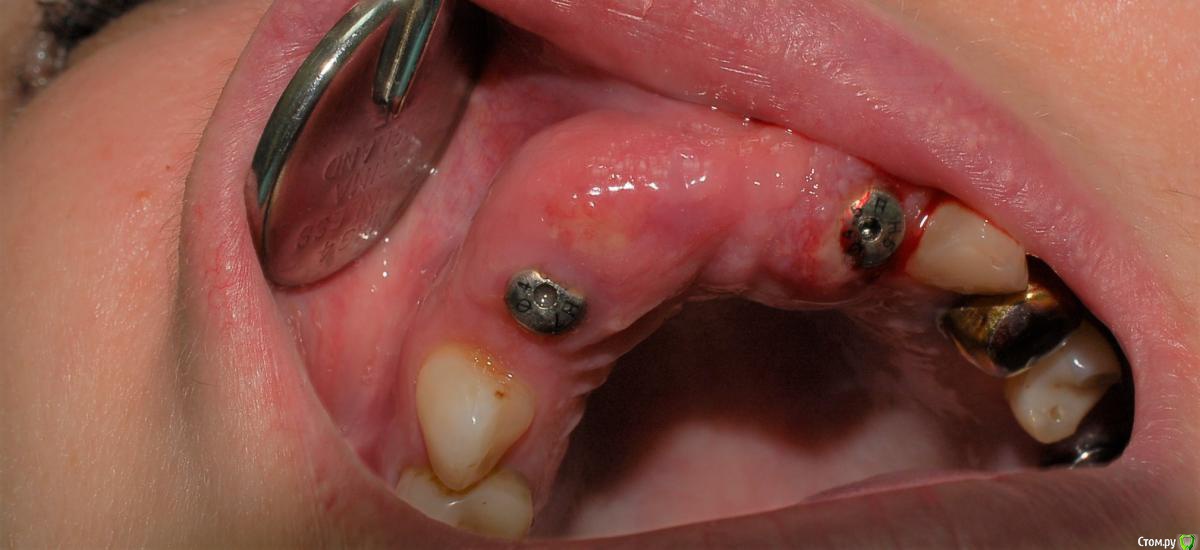

Jermano Опубликовано 19 января, 2020 Автор Поделиться Опубликовано 19 января, 2020 Наконец загрузил изображения. Выкрутил эти два ФДМа и сделал снимки уже с заглушками. Эти два передних Anyone, остальные Osstem. На этом снимке была установка с расщеплением, заглубление было достаточным. Но повторюсь мукозит вокруг всех 6 имплантов, кроме одного, который был установлен одноэтапно. Допрашивал с пристрастием, не курит, не пьёт, аллергоанамнез не отягощен. В понедельник сделает общий анализ крови. Болей нет. Ссылка на комментарий

Jermano Опубликовано 19 января, 2020 Автор Поделиться Опубликовано 19 января, 2020 а чем присыпали(когда ставили)?Вот сейчас всё выстраивается в логическую цепь. Все эти импланты присыпал ксено, не буду называть производителя, потому что ещё не уверен. Но это ксено я стал использовать 3 года назад, НИРАЗУ ещё проблем с этим графтом не было. Всегда его использую для одномоментных кейсов. Дело в том, что из 6 имплантов - 3 одномоментно с удалением, а два с расщеплением. Везде ксенографт. Кроме того в процессе установки был удален 11, там тоже он же. Вот в проекции этого зуба самое большое выбухание воспаленной десны, как видно на снимке. Здесь было самое большое количество графта. Думаю в процессе раскрытия произошло инфицирование графта, потому-что до раскрытия всё было спокойно. Почему это произошло пока предположений нет. Только один имплант простая установка, вот он в порядке. Ссылка на комментарий